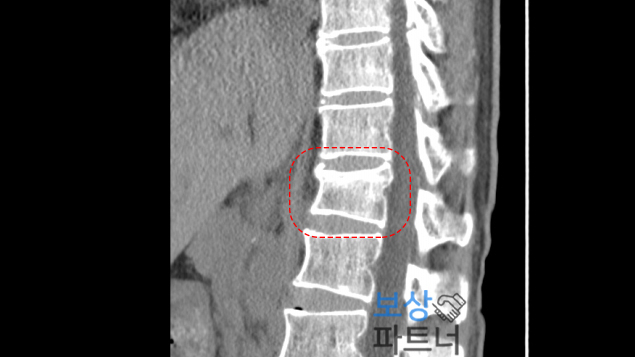

검사 결과, 허리뼈인 L1(제1요추)과 L4(제4요추)에 압박골절 진단을 받으셨습니다. 뼈가 약해지는 시기에는 가벼운 충격만으로도 척추가 납작하게 눌리는 압박골절이 발생하기 쉬우니 각별한 주의가 필요합니다.

시술 받았던 병원의 주치의는 장해평가에 비협조적이었기에 저희 보상파트너는 공신력 있는** 제3병원 전문의를 통해 장해평가를 진행하였습니다. 특히 심했던 요추1번 압박율을 측정한 결과 48%**로 확인되었고, 이는 보험약관 상 **척추에 뚜렷한 기형을 남긴 때 30%**에 해당하는 수치였습니다.